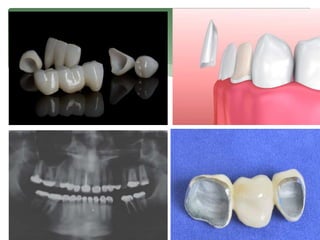

WHAT IS

BRIDGE

CROWN

VENEER

• Restores normal shape, size and function of tooth.

• Can make the tooth stronger or improve the looks.

• If the cavity is too large for a filling and large

fracture.

(cover or cap)

• Parts: abutment and pontic tooth.

• Abutment teeth: two or more crowns that go over the

natural teeth.

• Pontic tooth: a false tooth. Made from gold, alloys.

Porcelain or a combination.

Bridge (closes a gap created

by one or more missing

teeth, supported by natural

teeth or implants.)

• Thin tooth colored shells.

• Attached to the facial surface of teeth to improve

their appearance.

• Made from porcelain or resin composite material.

• Permanently bonded to teeth